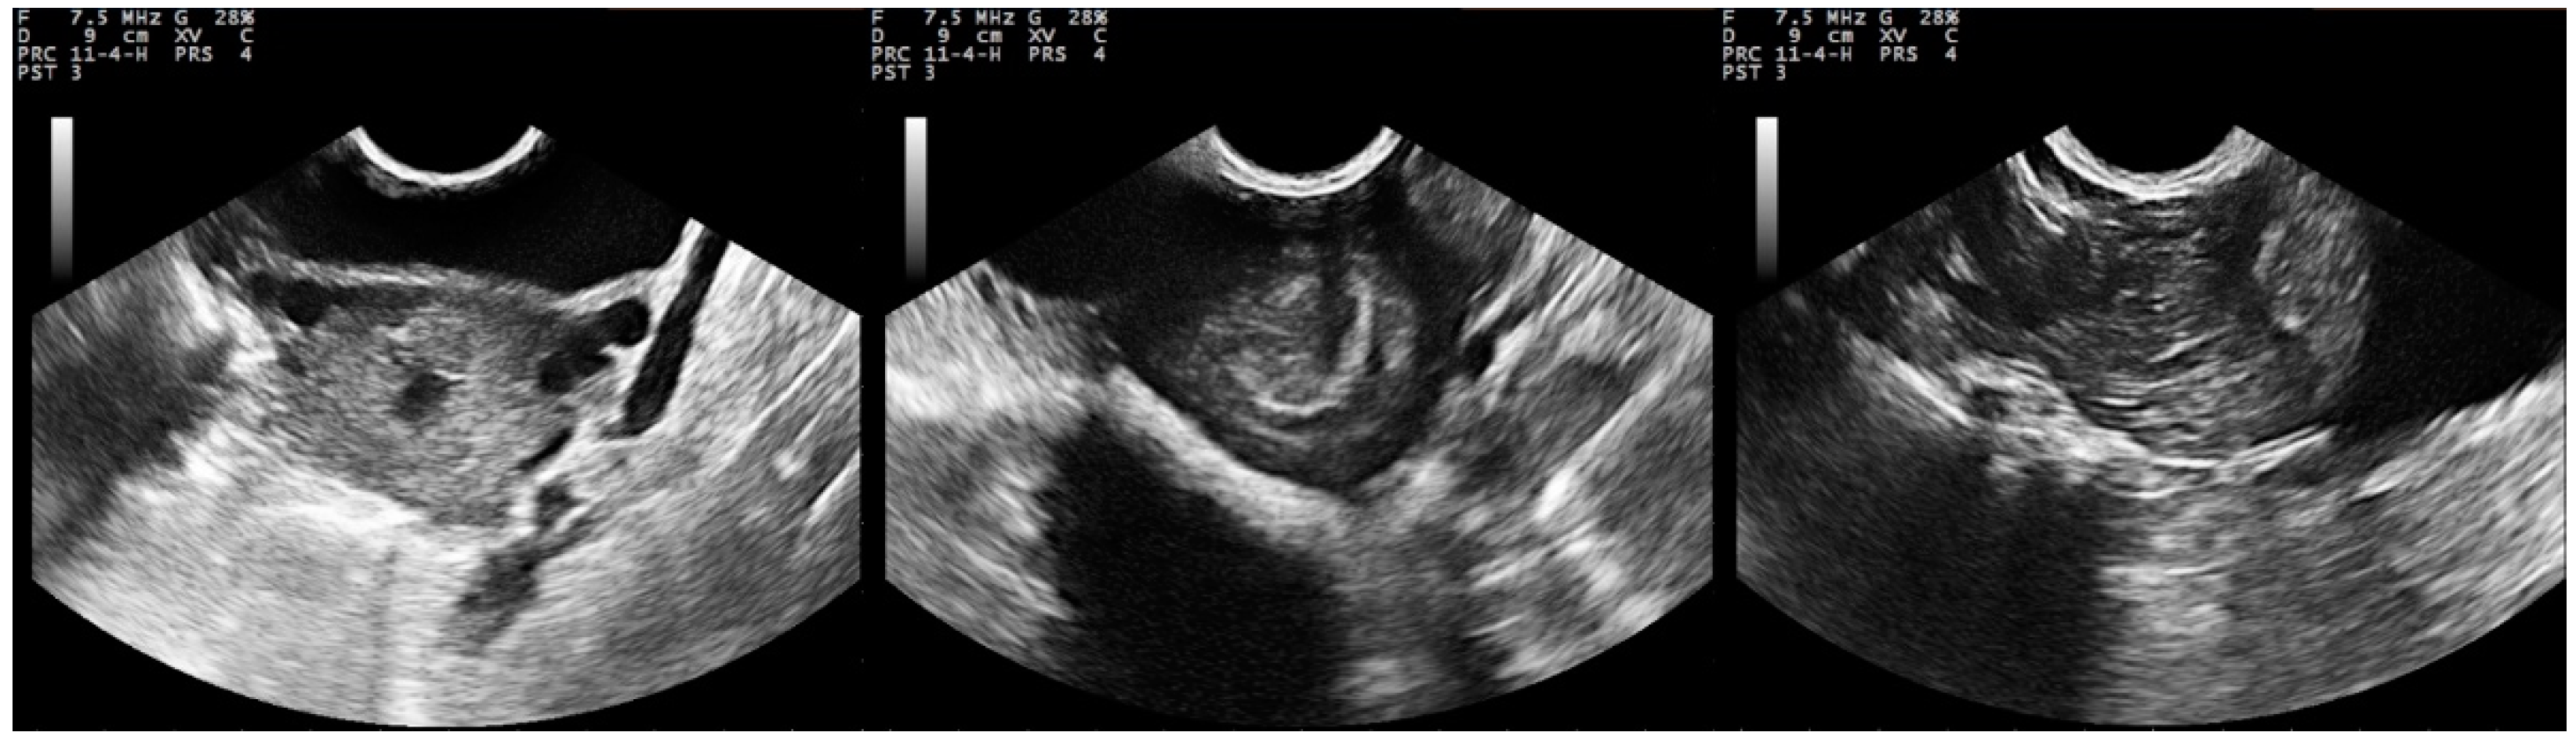

Distribution of various types of uterine lesions. Download Scientific Diagram

From www.researchgate.net

(PDF) Uterine infections definition, symptoms and diagnosis Types Of Uterine Infections    anyone with a uterus can get endometritis.  pelvic inflammatory disease (pid) is an infection of a woman’s reproductive tract. Postpartum infections are described by the three distinct areas where they may occur ,. Endometritis is one of the most common infections after you give birth.   what are the types of puerperal infections? It can affect the uterus,. Types Of Uterine Infections.